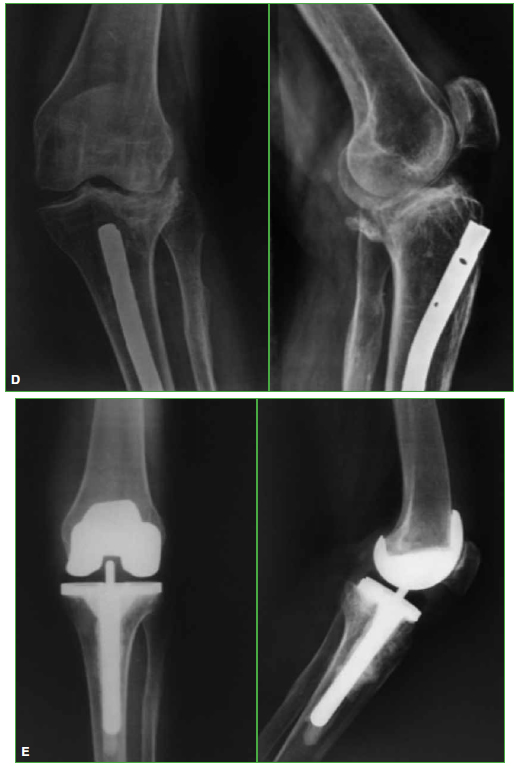

Artroplastia total de rodilla en pacientes con secuela de fracturas articulares. Resultados del seguimiento a mediano plazo

Acceso mediante suscripción PDF Acceso mediante suscripción PDF_EN (English) Acceso mediante suscripción HTML Acceso mediante suscripción Figura 1 (a-c) Acceso mediante suscripción Figura 1 (d-e) Acceso mediante suscripción Figura 1 (f) Acceso mediante suscripción Tabla 1 Acceso mediante suscripción Tabla 2 Acceso mediante suscripción Tabla 3 Acceso mediante suscripción Tabla 4